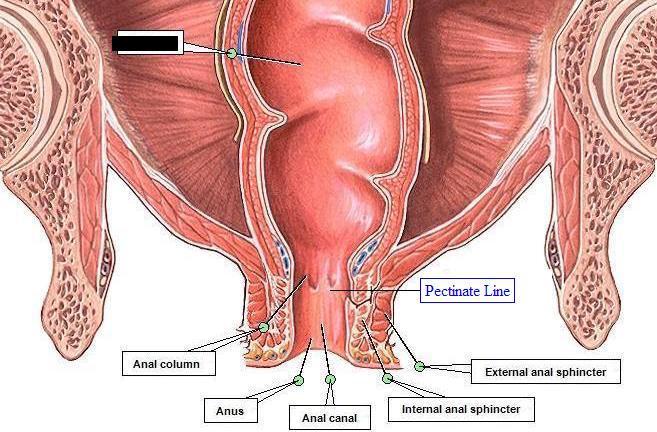

Anal Canal

Anus